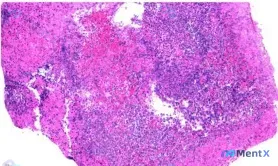

整理到一份回盲部及升结肠病变的资料,有点意思,也有点陷阱: 初始病理只提了回盲部黏膜坏死、出血、炎症; 进一步影像分析看到了组织架构完全破坏、大片凝固性坏死、弥漫性“异型细胞”,直接指向了高级别恶性肿瘤伴坏死; 但还有另一种声音——这个位置、这个形态,会不会是感染/缺血的形态学假象?比如结核的干酪样...